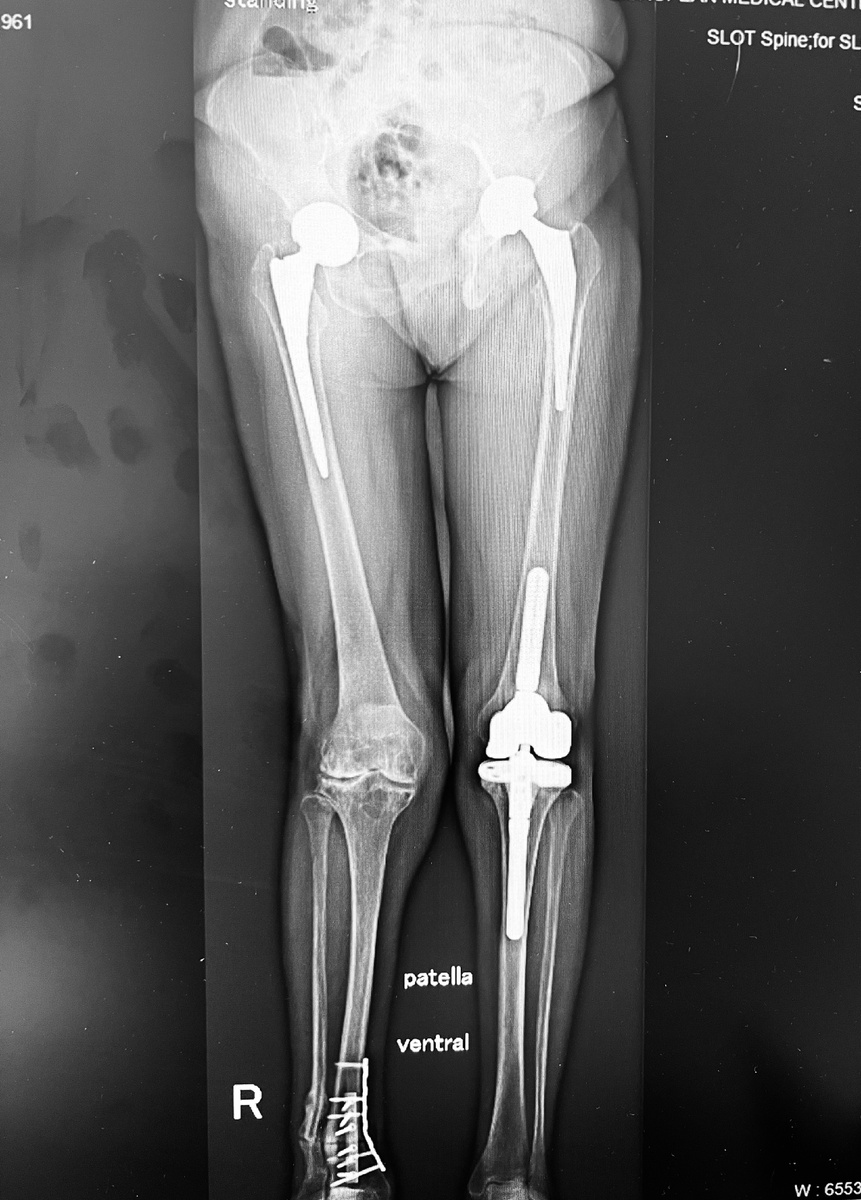

Вот одна из моих пациенток, первая операция которой (правый тазобедренный сустав) была сделана в 2011 году. В промежутках между тазобедренными и коленными - стопы, корригирующая остеотомия голени. Всего 7 или 8 операций. Последняя - замена правого коленного сустава.

А после операции так:

-3

Никаких проблем с крупными суставами. Шесть месяцев после последней операции.